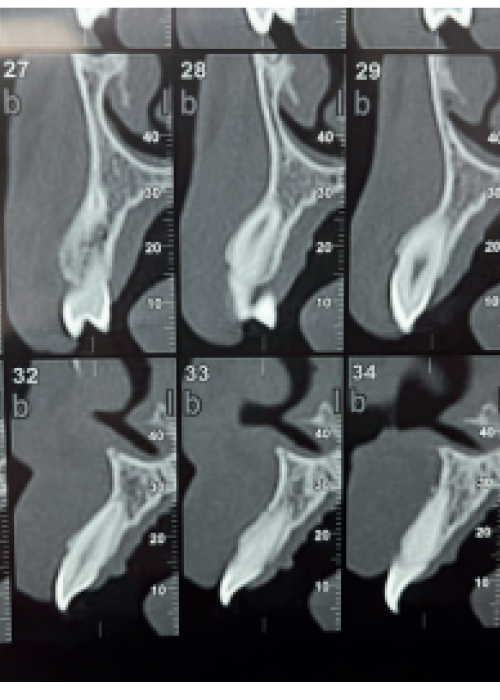

Clinical, radiographic and histomorphometric behaviour of the autologous tooth as a biomaterial in lateral access maxillary sinus elevation. Case report with six months of post-prosthetic loading follow-up

Comportamiento clínico, radiográfico e histomorfométrico del diente autólogo como biomaterial en elevación de seno maxilar de acceso lateral. Caso clínico con seis meses de seguimiento post-carga protésica